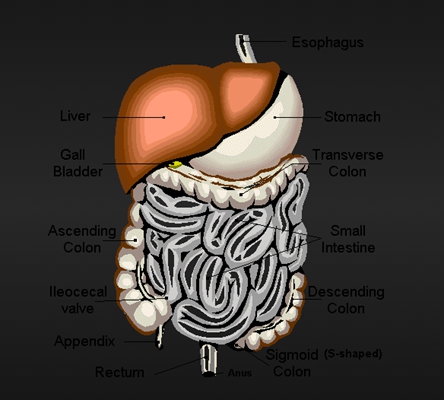

盲腸的位置 (50)

盲腸的位置 (6)

盲腸的位置 (7)

盲腸的位置 (8)

盲腸的位置 (9)

盲腸的位置 (46)

盲腸的位置 (47)

盲腸的位置 (48)

盲腸的位置 (49)

盲腸的位置 (5)

盲腸的位置 (42)

盲腸的位置 (43)

盲腸的位置 (44)

盲腸的位置 (45)

盲腸的位置 (41)

盲腸的位置 (40)

盲腸的位置 (30)

盲腸的位置 (31)

盲腸的位置 (32)

盲腸的位置 (33)